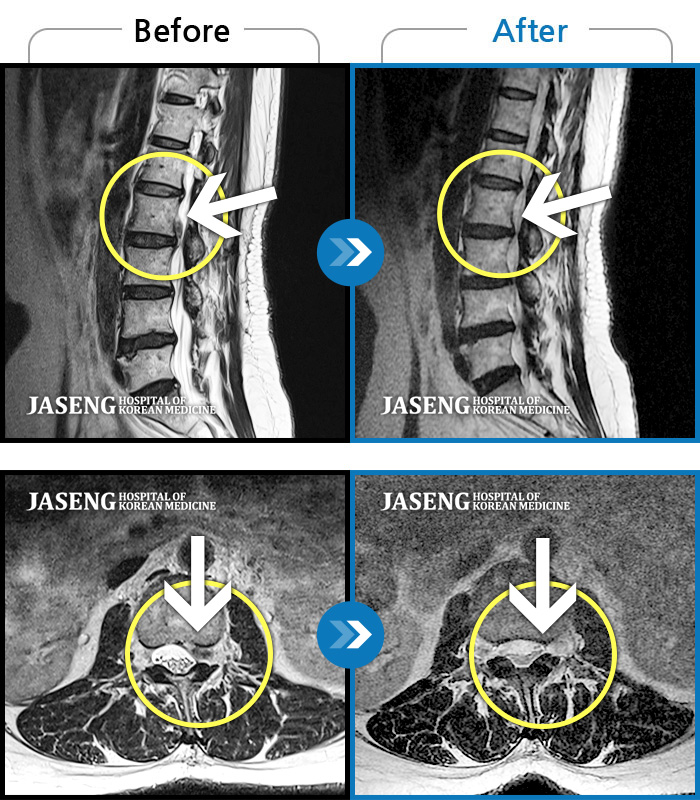

허리디스크

일산 · 배영현 원장

처음 내원 시 허리, 엉덩이가 많이 아프고, 좌측 다리에 힘이 빠지며 감각이 둔하여 정상적인 보행이 힘든 상태셨습니다.

촬영시기

2022.05.24 ~ 2023.05.13

2023.06.01